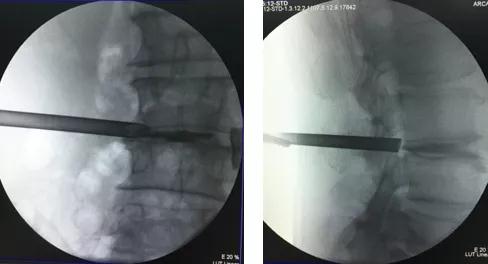

▲椎间盘造影,便于医生镜下快速辨识突出的椎间盘

▲术中靶向穿刺置管

整个手术没有传统手术的紧张氛围,仅在局麻下进行,患者全程保持清醒。手术中,赵叔右大腿的痹痛即刻缓解,右侧股神经牵拉试验(-)阴性,恢复正常!手术伤口仅有“1厘米”,术后第一天,赵叔已经可以佩戴腰围下地活动了,之前站立及行走的疼痛症状也随微创手术消失。